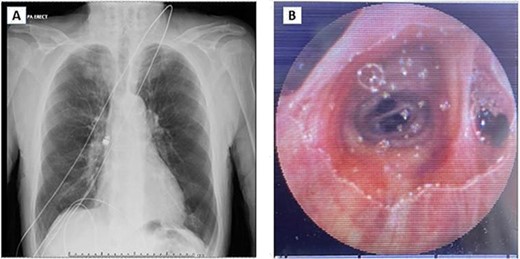

(A) Chest X-ray showing capsule in the right main bronchus. (B) Capsule lodged in bronchus intermedius showing endobronchial anatomy.

Post review, the patient consented to rigid/flexible bronchoscopy and retrieval of a foreign body. Because of the prevalent coronavirus disease 2019 (COVID-19) pandemic, the procedure was performed with full COVID precautions. A flexible bronchoscope evaluation was performed with the patient under general anaesthesia and through a size 8.5 endotracheal tube (ETT). The capsule was found to be lodged in the bronchus intermedius (Fig. 1B). The size of the capsule (26.2 × 11.4 mm) and its very smooth surface meant that it could not be grasped by available endobronchial instruments. Attempts to trap it in a Nitnol tipless stone extractor basket (2.2 cm) were not successful. We subsequently tried using Fogarty catheters (of sizes 3–7). Although we were able to dislodge the capsule into the trachea, the size discrepancy between the balloon and trachea and perhaps because of the weight of the capsule, it could not be delivered into the upper trachea it repeatedly slipped back to the bronchus on the right. Because of this repeated slippage, the patient was placed in a stip Trendelenburg position. The use of gravity prevented slippage of the capsule distally. After this manoeuvre, the capsule was drawn to the tip of the ETT. The capsule was wedged between the balloon of the Fogarty and the ETT tip and they were all withdrawn as a unit (Fig. 2). The capsule was brought outside the vocal cords and retrieved using Magill forceps. The patient was subsequently reintubated until subsequent extubation. The postoperative recovery was uneventful.